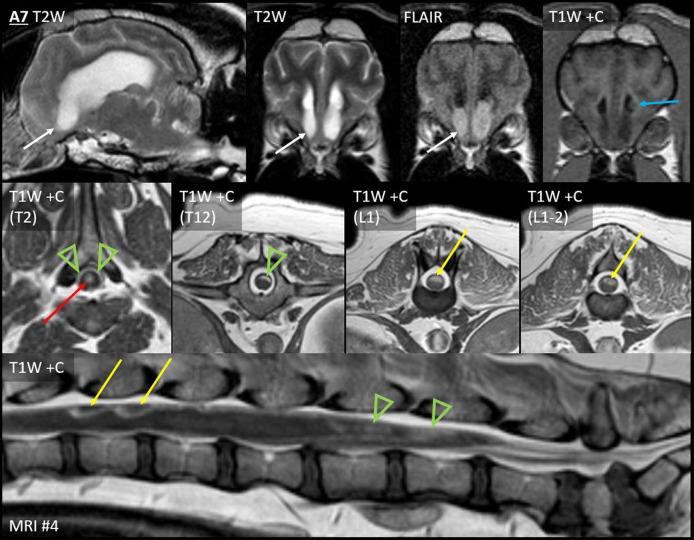

犬胶质瘤的脑脊液播散转移:磁共振成像分类

Dissemination of glioma in humans can occur as leptomeningeal nodules, diffuse leptomeningeal lesions, or ependymal lesions. Cerebrospinal fluid (CSF) drop metastasis of glioma is not well-recognized in dogs. Ten dogs with at least two anatomically distinct and histologically confirmed foci of glioma were included in this study. The 10 dogs underwent 28 magnetic resonance imaging (MRI) examinations, with distant CSF drop metastasis revealed in 13 MRIs. The CSF drop metastases appeared as leptomeningeal nodules in four dogs, diffuse leptomeningeal lesions in six dogs, and ependymal lesions in seven dogs; six dogs had a combination of lesion types. Primary tumors were generally T2-heterogeneous and contrast-enhancing. Many metastases were T2-homogeneous and non-enhancing. Diffuse leptomeningeal lesions were seen as widespread extra-axial contrast-enhancement, again very dissimilar to the intra-axial primary mass. Primary masses were rostrotentorial, whereas metastases generally occurred in the direction of CSF flow, in ventricles, CSF cisterns, and the central canal or leptomeninges of the cervical or thoracolumbar spinal cord. Seven of the dogs had received therapy limited to the primary mass, such as surgery or stereotactic radiation, then developed metastasis in the following months. CSF drop metastasis of glioma may take a very different appearance on MRI to the primary mass, including periventricular lesions that are more homogeneous and less contrast-enhancing, rostral horn signal changes, or leptomeningeal enhancement ventral to the brainstem or encircling the spinal cord.

胶质瘤在人类中的播散可表现为软脑膜结节、弥漫性软脑膜病变或室管膜病变。胶质瘤的脑脊液播散转移在犬类中尚未得到充分认识。本研究纳入了10只患有至少两个解剖学上不同且经组织学证实的胶质瘤病灶的犬。这10只犬接受了28次磁共振成像(MRI)检查,其中13次MRI显示有远处脑脊液播散转移。脑脊液播散转移在4只犬中表现为软脑膜结节,6只犬中表现为弥漫性软脑膜病变,7只犬中表现为室管膜病变;6只犬有多种病变类型组合。原发性肿瘤通常在T2加权像上呈不均匀信号且有强化。许多转移灶在T2加权像上呈均匀信号且无强化。弥漫性软脑膜病变表现为广泛的脑外强化,与脑内原发性肿块截然不同。原发性肿块位于前脑幕区,而转移灶通常沿脑脊液流动方向发生,见于脑室、脑池、中央管或颈段或胸腰段脊髓的软脑膜。7只犬接受了局限于原发性肿块的治疗,如手术或立体定向放疗,随后在接下来的几个月内出现了转移。胶质瘤的脑脊液播散转移在MRI上的表现可能与原发性肿块非常不同,包括更均匀且强化较少的脑室周围病变、脑室前角信号改变,或脑干腹侧或脊髓周围的软脑膜强化。